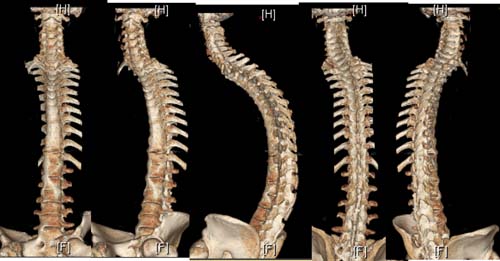

术前影像图像

术前手术设计